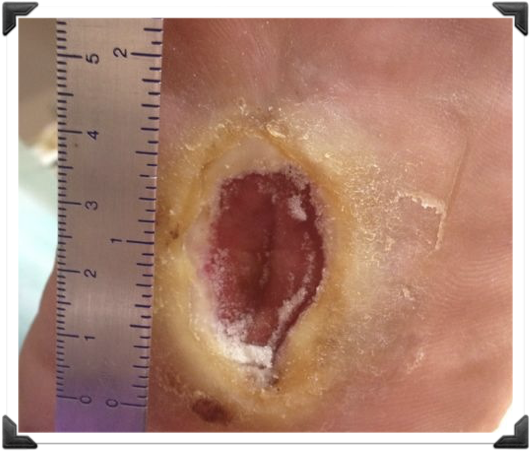

Caso Clínico Pie de Riego

- Profiláctico y Terapeutico

- Femenino 60 años

- Cirugia Fallida

- Tecnica Abierta Canadiense

Caso Clínico Pie de Riego

Profiláctico y Terapeutico

Post op Clínico

- Osteotomía Cuña Dorsal 1er Dedo

- Tenotomia del Flexor del 1er Dedo

- Osteotomía de Falange 2do Dedo

Puede ser procedimiento de Consultorio